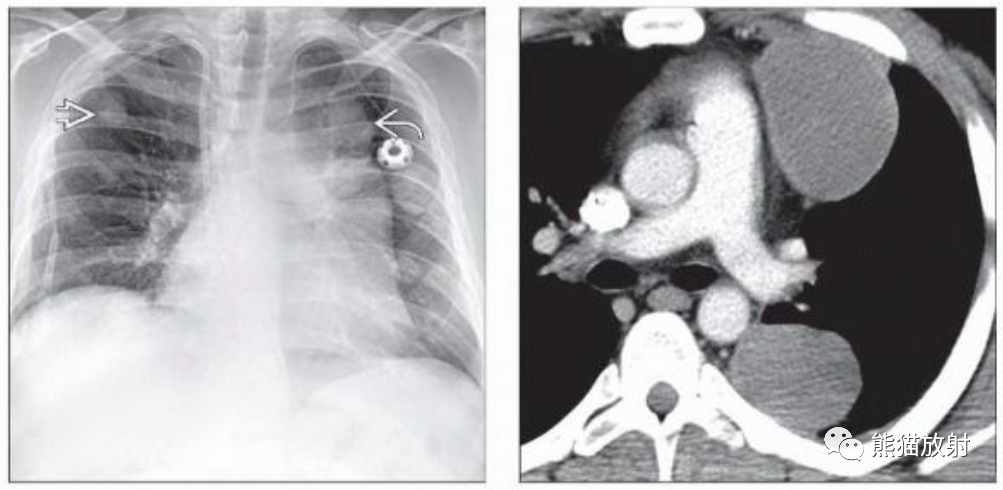

(左)30岁男性,混合型纵隔恶性生殖细胞肿瘤。PA胸片显示左前纵隔分叶状肿块,另见数个肺结节,符合转移灶。

(右)同一患者,轴位CECT显示左前纵隔不均匀强化的软组织肿块和左后胸膜转移。原发性纵隔恶性生殖细胞瘤是高度侵袭性病变,通常在诊断时已转移。